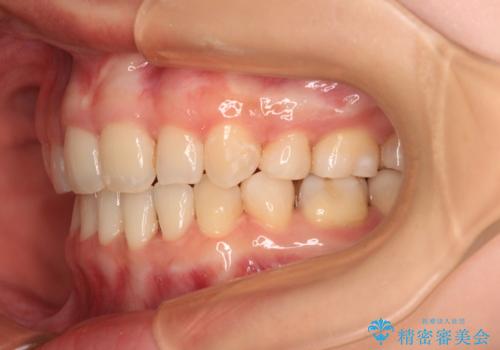

舌の突出癖の影響もあり、非抜歯矯正で治療開始したものの口元が突出し、唇が閉じにくくなってしまったため、途中で第一小臼歯4本を抜歯ししました。

口元の突出感のない、すっきりとした仕上がりとなりました。